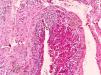

The lesion was completely extirpated, under local anesthesia. Postoperative progression was satisfactory, with symptom remission and healing of the surgical wound. The histopathologic study reported Masson’s tumor with intravascular papillary endothelial hyperplasia (Figs. 2 and 3).

Masson’s pseudoangiosarcoma accounts for just 2% of all vascular tumors of the skin and soft tissues.2 Only two cases with an anal location are reported in the literature,3 but no cases of perianal location have previously been described. The morphologic characteristics of the cases reported at other areas of the body are similar to those of the case presented herein.4 These tumors have an excellent prognosis but making the differential diagnosis with other entities, especially with angiosarcomas, is necessary.5 In contrast to malignant lesions, pseudoangiosarcomas do not present with necrosis, atypic elements, or mitotic figures.6